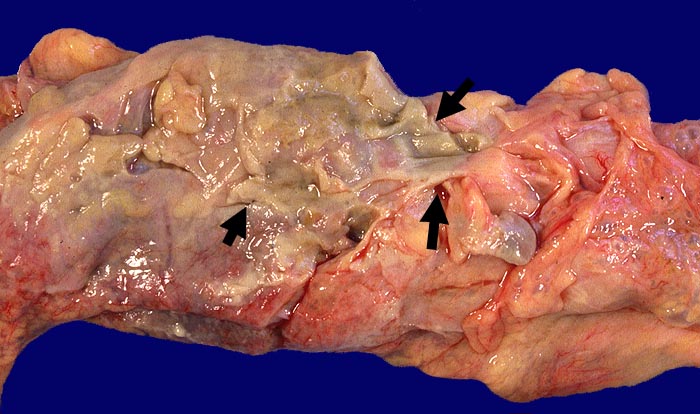

Fibrinös eitrige Peritonitis bei perforierter Sigmadivertikulitis

Schmutzig grau-gelbe ► Auflagerungen auf der Serosa.